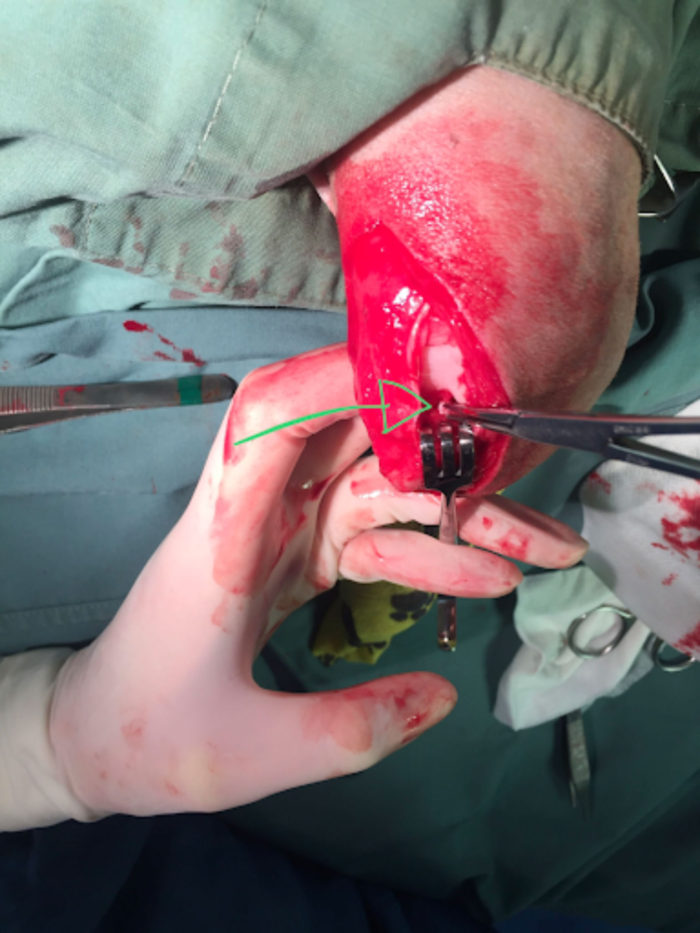

Many surgical options have been described to address the stifle instability that occurs with CrCL disease. At the present time, the most commonly performed operations include the lateral fabellotibial suture, tibial tuberosity advancement (TTA), and tibial plateau-leveling osteotomy (TPLO). With all these surgical procedures, the joint is surgically opened and examined, both meniscus are inspected for tears and any torn portions are removed. In most cases the damaged cruciate ligament is also debrided.

The picture above shows the torn CrCL visible during exploration of the stifle joint (arrow)